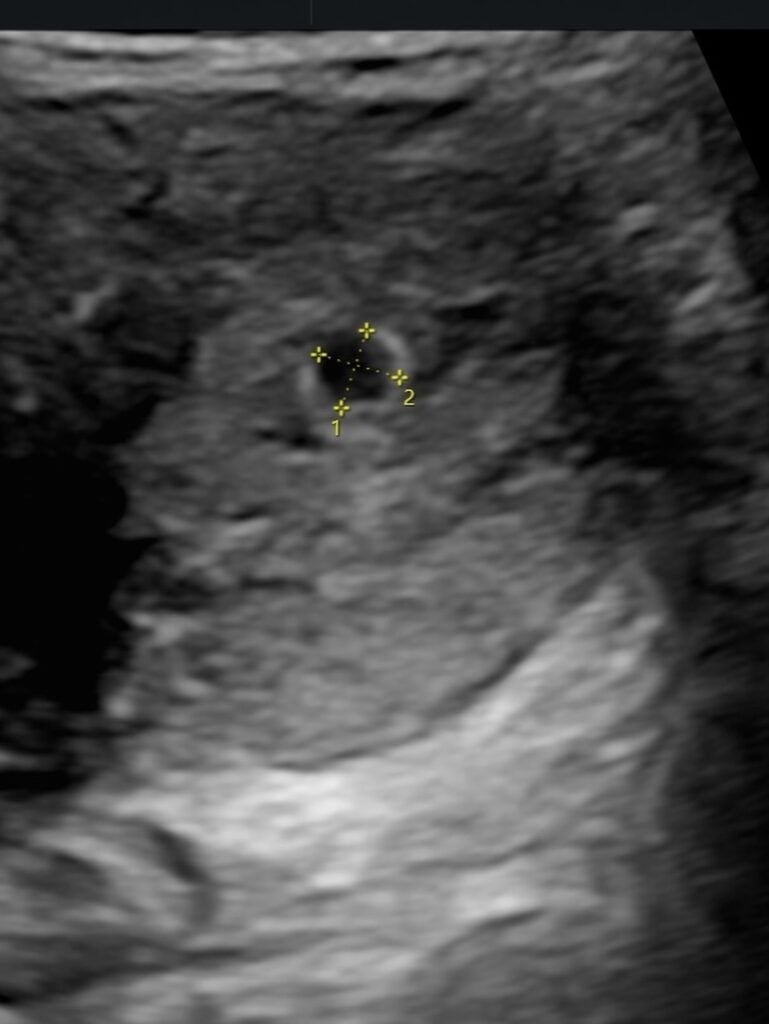

貼文中,她也公開第一次產檢的超音波照片,因為畫面看起來像兔子,夫妻倆替寶寶取了小名「Tokki」,並溫柔寫下:「會等你準備好再回來。」同時,她也向正在努力懷孕、或正在接受試管療程的媽媽們喊話,表示「你們不孤單」,用自身經歷傳遞陪伴與支持。